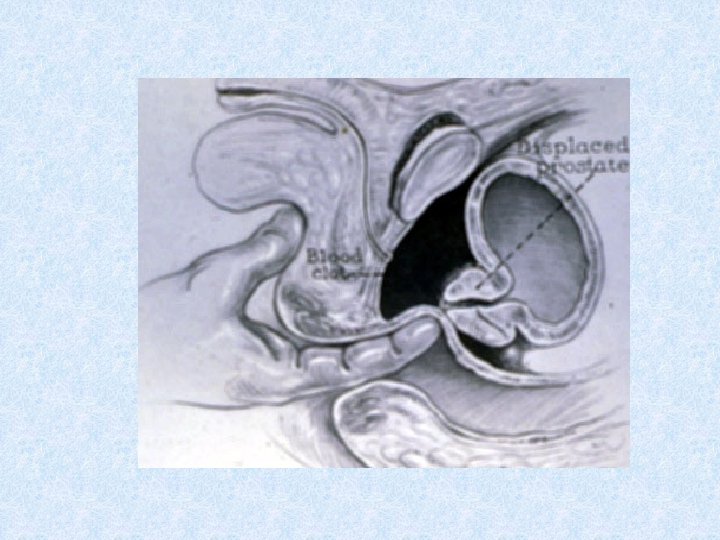

Urethral Trauma Mechanism of Injury • Posterior injury usually accompanies pelvic fractures • Trauma to anterior urethra usually isolated • Trauma to posterior urethra usually co-exists with damage to other structures • Sudden deceleration injuries (bladder shears off urethra)

Signs and Symptoms of Urethral Trauma • Suprapubic pain • Urge to urinate but are unable • Hematuria (may be microscopic) • Blood at external meatus • Perineal butterfly eritem • • Scrotal Hematoma Rebound tenderness Abdominal wall muscle rigidity Displaced prostate gland during rectal exam

Posterior Urethral Injuries • 80 -90% occur in combination with pelvic fracture • 10 -25% of pelvic ring fractures disrupt posterior urethra as puboprostatic ligaments are torn or stretched • Associated with bladder injuries and vaginal lacerations